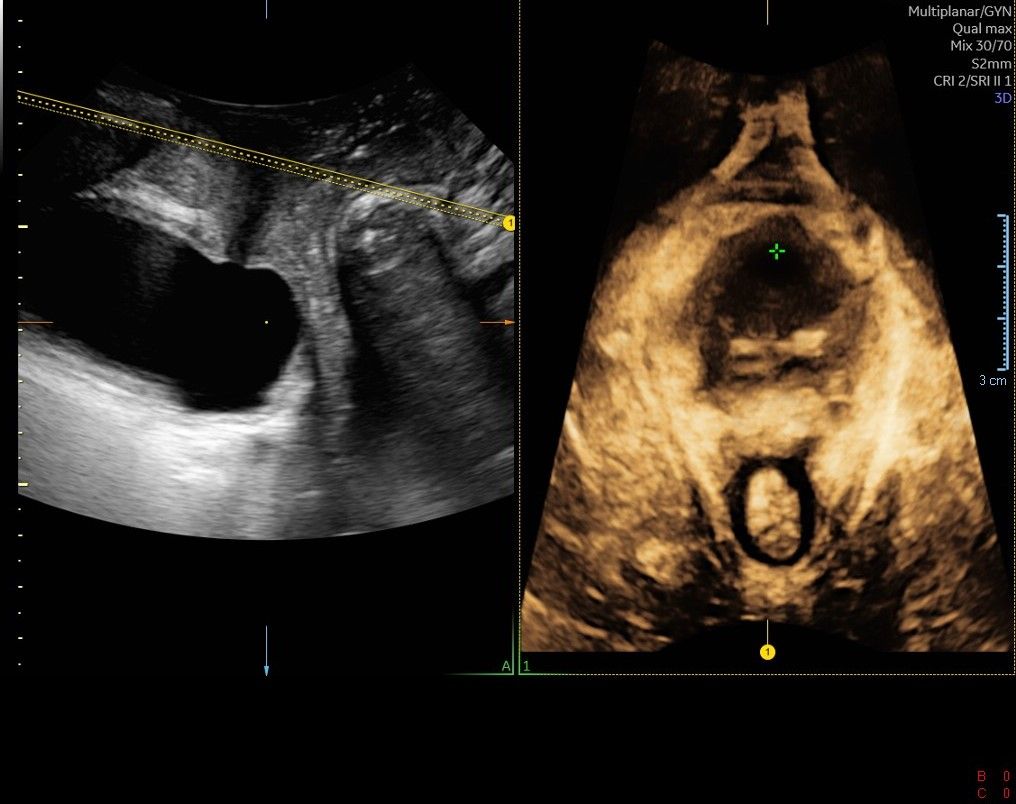

Eseguo in particolare ecografie ostetriche e ginecologiche anche in 3D e 4D per meglio identificare la problematica, offrire diagnosi precise ed un trattamento mirato e personalizzato.